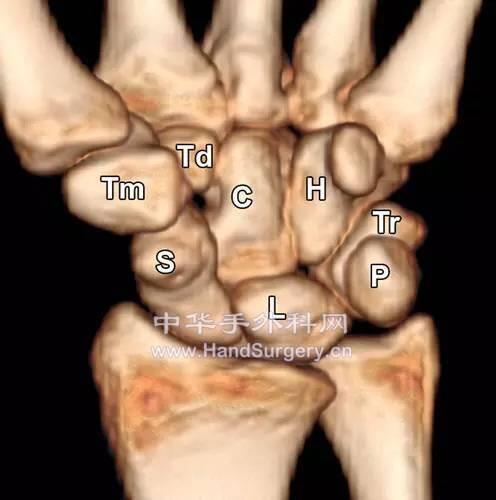

腕关节Gilula线

楼主| 发表于 2020-5-10 23:48:59 | 显示全部楼层

侧位